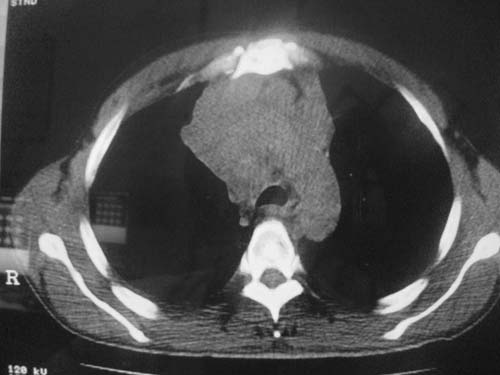

以下是引用科室第一人在2010-3-25 20:30:00的发言:[br]1:纵膈肿瘤性病变,恶性胸腺瘤可能性大伴纵膈右肺门淋巴结转移,右侧胸腔积液。[br]2:右侧肺门肿瘤性病变,纵膈淋巴结转移,右侧胸腔积液。右下叶转移。

以下是引用子期在2010-3-25 21:00:00的发言:[br]先考虑右中央型肺癌伴转移。

以下是引用江广1996在2010-3-25 22:49:00的发言:[br]通常肺癌向纵隔转移多见,纵隔肿瘤向肺内转移少见(有的表现为向肺内侵润)。本例以一元论考虑:右中心型肺癌并纵隔淋巴等多处转移。[br][br][本贴已被 江广1996 于 2010-3-25 22:50:07 修改过]

以下是引用yangyudong333在2010-3-26 6:43:00的发言:[br]“冰冻纵膈”,考虑纵膈淋巴瘤伴肺内及胸膜侵润。